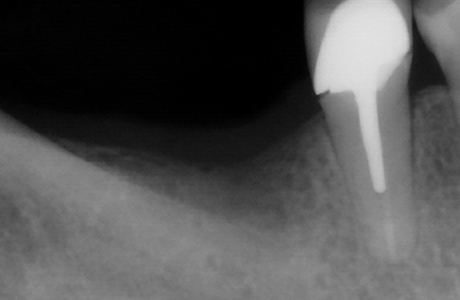

Пациентка обратилась в клинику за установкой зуба, удалённого более года назад, с целью восстановления жевательной функции. Врач стоматолог-терапевт, хирург, имплантолог, ортопед Шандро Евгения Богдановна провела осмотр и анализ компьютерной томографии, после чего принято решение установки импланта Alpha Bio в позицию зуба 4.6.

- установка импланта Alpha Bio;